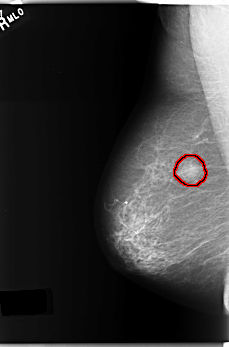

C_0231_1.LEFT_MLO

FILE: C_0231_1.LEFT_MLO.OVERLAY

TOTAL_ABNORMALITIES 1

ABNORMALITY 1

LESION_TYPE CALCIFICATION TYPE PLEOMORPHIC DISTRIBUTION CLUSTERED

ASSESSMENT 4

SUBTLETY 5

PATHOLOGY BENIGN

TOTAL_OUTLINES 1

BOUNDARY